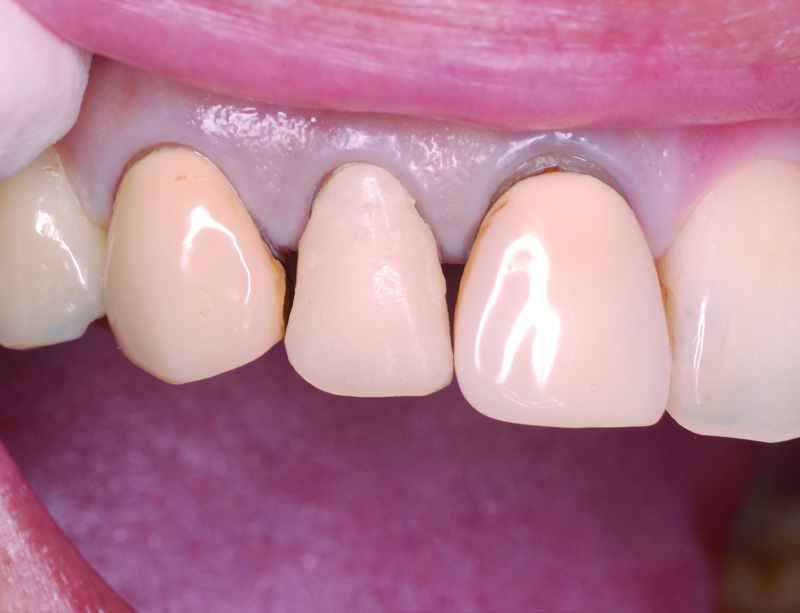

術前の状態です。右上中切歯の被せ物が合っていないことがわかります。また周りの歯の樹脂も劣化が認められます。

被せ物を外すとう蝕が認められました。

土台外すとさらに根管の中にもう蝕が認められました。

残っている歯の量が少ないため、根管治療後に部分矯正にて歯を引っ張り上げる(矯正的挺出)こととしました。

その際は表には仮歯をつけて見た目の確保を行います。

矯正的挺出が終わった状態です。歯とともに歯肉と骨も一緒に引っ張り上げられるので、

手術(歯冠長延長術)によって歯肉と骨を整形し、健康な歯の量を確保します。

歯冠長延長術を行ったところです。

その後土台を築造し、型取りを行います。

右上中切歯にセラミッククラウンを装着して、周りの歯の樹脂もやり替えを行いました。